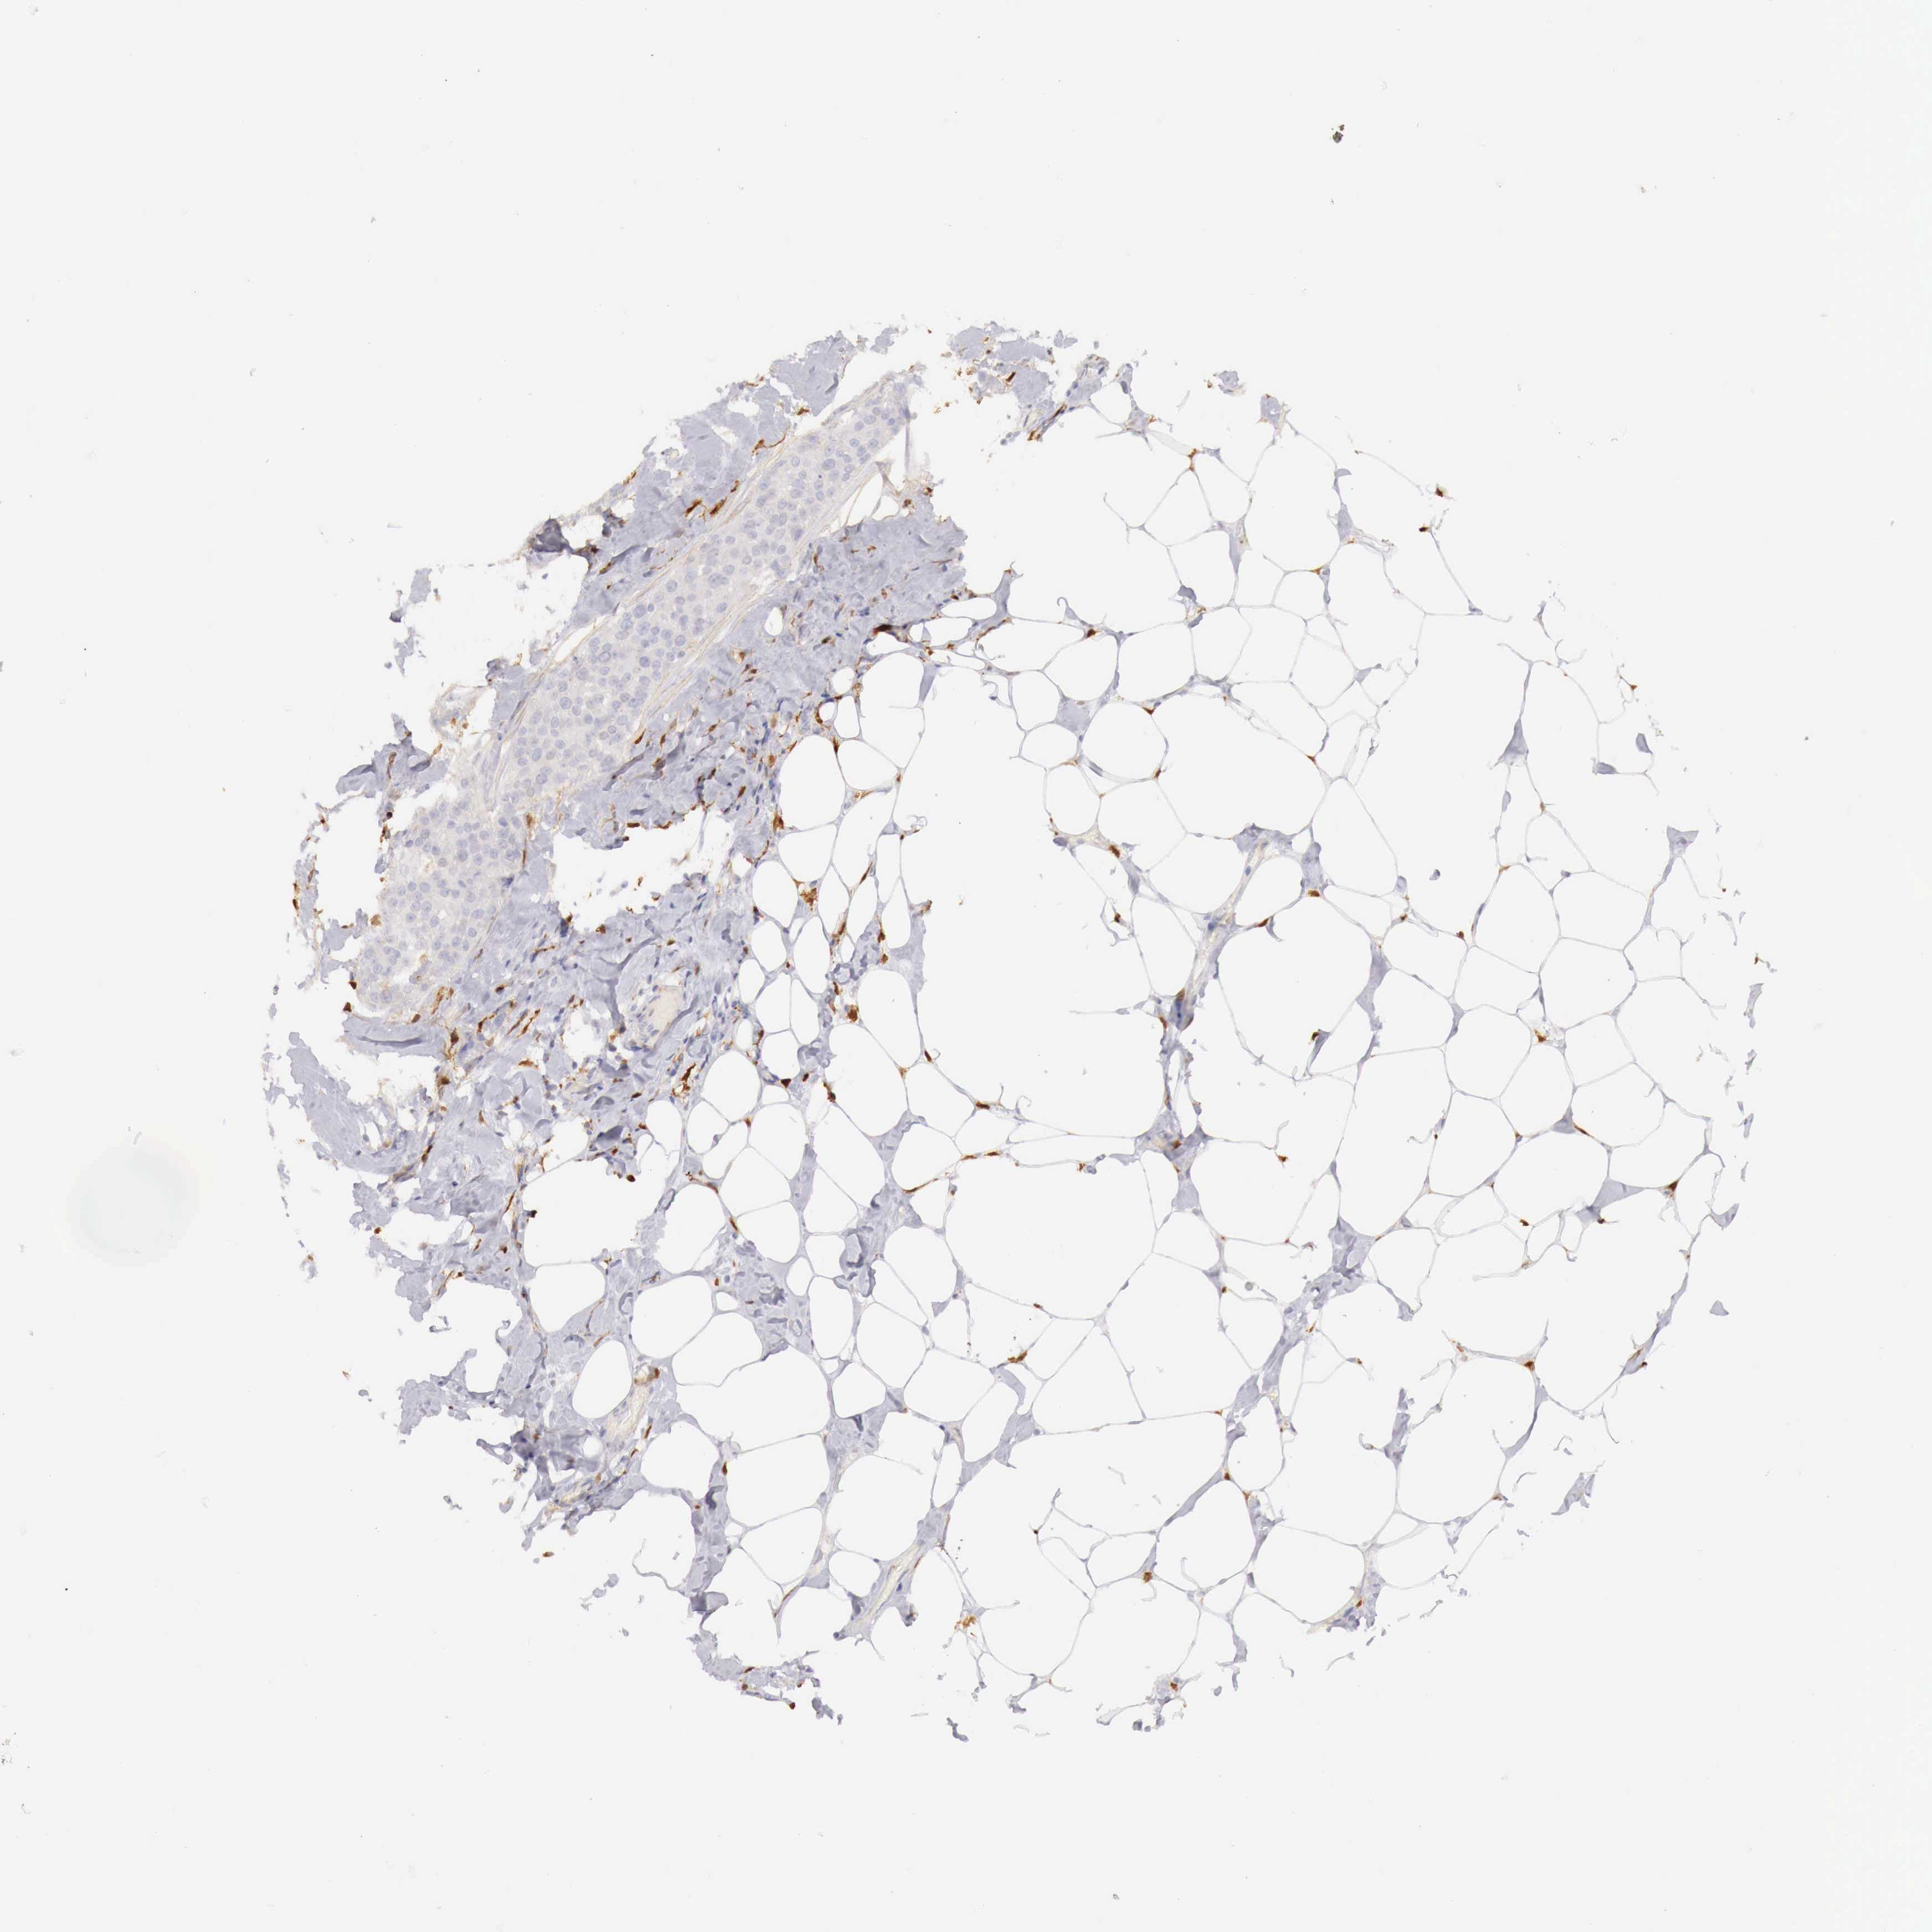

CANCER BREAST CANCER Show tissue menu

BRCA TCGA BRCA VALIDATION PROTEIN EXPRESSION